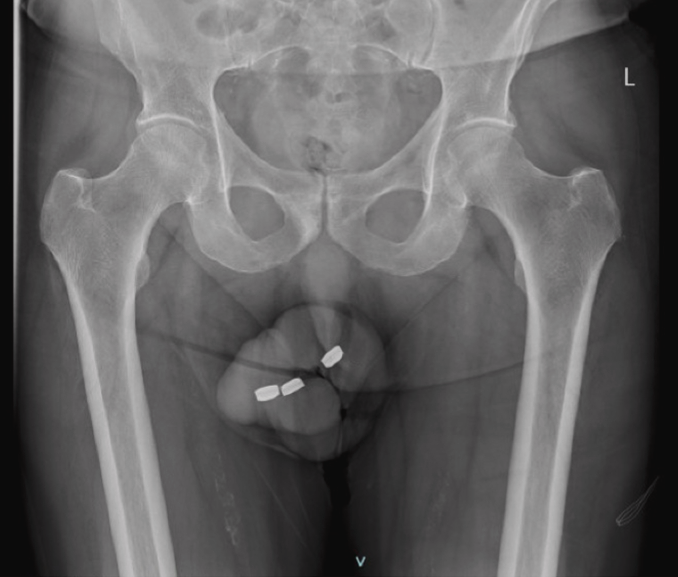

Les cas de corps étrangers insérés dans les orifices qui nécessitent une intervention médicale pour les retirer sont légion. Et malheureusement, par honte ou par peur de l’humiliation, certains patients ne consultent pas immédiatement, ce qui peut avoir des conséquences très graves. Un Australien de 73 ans en a d’ailleurs récemment fait les frais après avoir inséré trois piles boutons de plus d’un centimètre dans son urètre pénien, le canal urinaire de sortie de la vessie.

Lorsqu’il se présenta aux urgences de l’hôpital de Footscray (banlieue de Melbourne, Australie), celui que la toile surnomme aujourd’hui l’Energizer dummy (« l’andouille Energizer », NDLR) l’assurait pourtant : ce n’était pas la première fois qu’il insérait des piles rondes dans son urètre à des fins d’autosatisfaction. Jusqu’ici, il avait toujours réussi à retirer ces objets de 13,3 mm de large et 3,2 mm d’épaisseur qu’il utilisait pour atteindre le nirvana. Néanmoins, cette fois, la situation dégénéra irrémédiablement pour ce patient resté anonyme. Voyant qu’il ne pouvait pas les retirer, ce n’est toutefois qu’après 24 h qu’il se résolut finalement à consulter. Il se plaignait alors de douleurs péniennes modérées, d’une faiblesse du jet (signe d’obstruction urinaire) et d’une sensation de vidange vésicale incomplète.

« Les piles boutons sont corrosives et lorsqu’elles sont insérées dans l’urètre, elles peuvent provoquer une liquéfaction et une nécrose des tissus. Un retrait urgent est nécessaire pour prévenir d’autres lésions tissulaires et complications », expliquent les médecins dans leur étude de cas publiée dans l’Urology Case Report. Ils durent donc prendre en charge le cas sans attendre pour espérer sauver leur patient, craignant notamment que le cas dégénère en gangrène de Fouiner, une infection nécrosante rare, mais létale.

Pour ce faire, ils eurent dans un premier temps recours à une pince à stent, puis une pince à artères sans toutefois arriver à libérer les corps étrangers. Cette procédure fut par ailleurs mal supportée par le patient. Après l’installation d’une intraveineuse pour lui administrer une batterie d’antibiotiques (sans mauvais jeu de mots) pour réduire le risque de gangrène, l’homme fut transféré d’urgence au bloc opératoire où les chirurgiens purent finalement extraire les piles par guidage cystoscopique, non sans s’inquiéter de leur aspect noir, recouvert d’une pellicule ressemblant à du goudron.